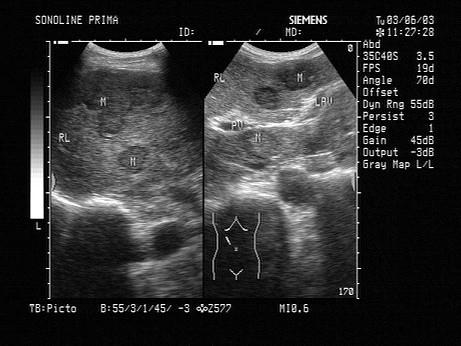

如图可诊断为?(?)A.小肝癌B.肝转移癌C.肝脓肿D.多发肝血管瘤E.肝囊肿

选项 A.小肝癌 B.肝转移癌 C.肝脓肿 D.多发肝血管瘤 E.肝囊肿

答案 B